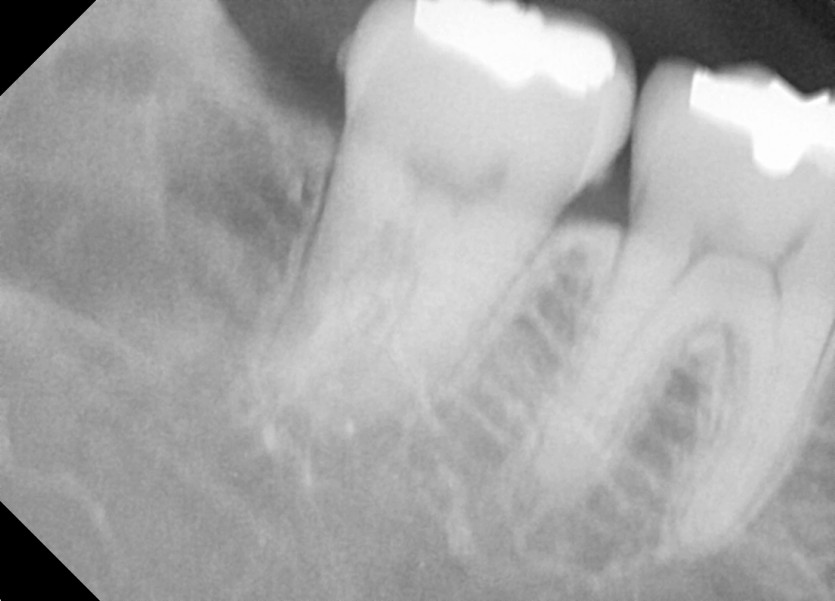

#48 사랑니 발치

구강외과 전문의가 당일발치 했습니다.